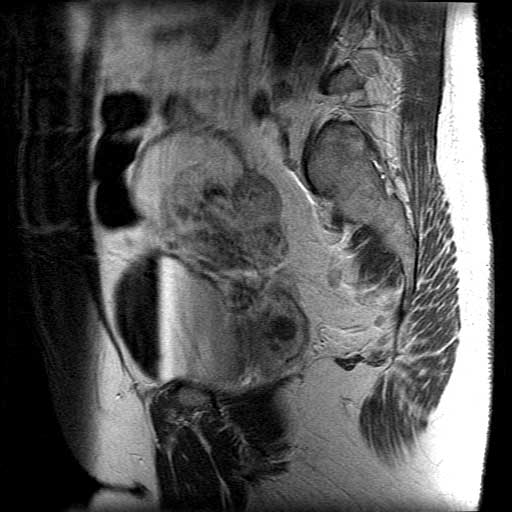

No.58症例6:47歳、女性 1G1P

41歳時に月経困難症にて当院受診、MRIにてendometriosis、adenomyosis、myoma uteriと診断される.GnRH agonist、低容量ピルを投与されていたが、1年半前より休薬していた.

定期受診にて左卵巣腫大を疑われ、精査加療目的にて入院.

CA19-9 43.9(<37)、CA125 375.2(<35)